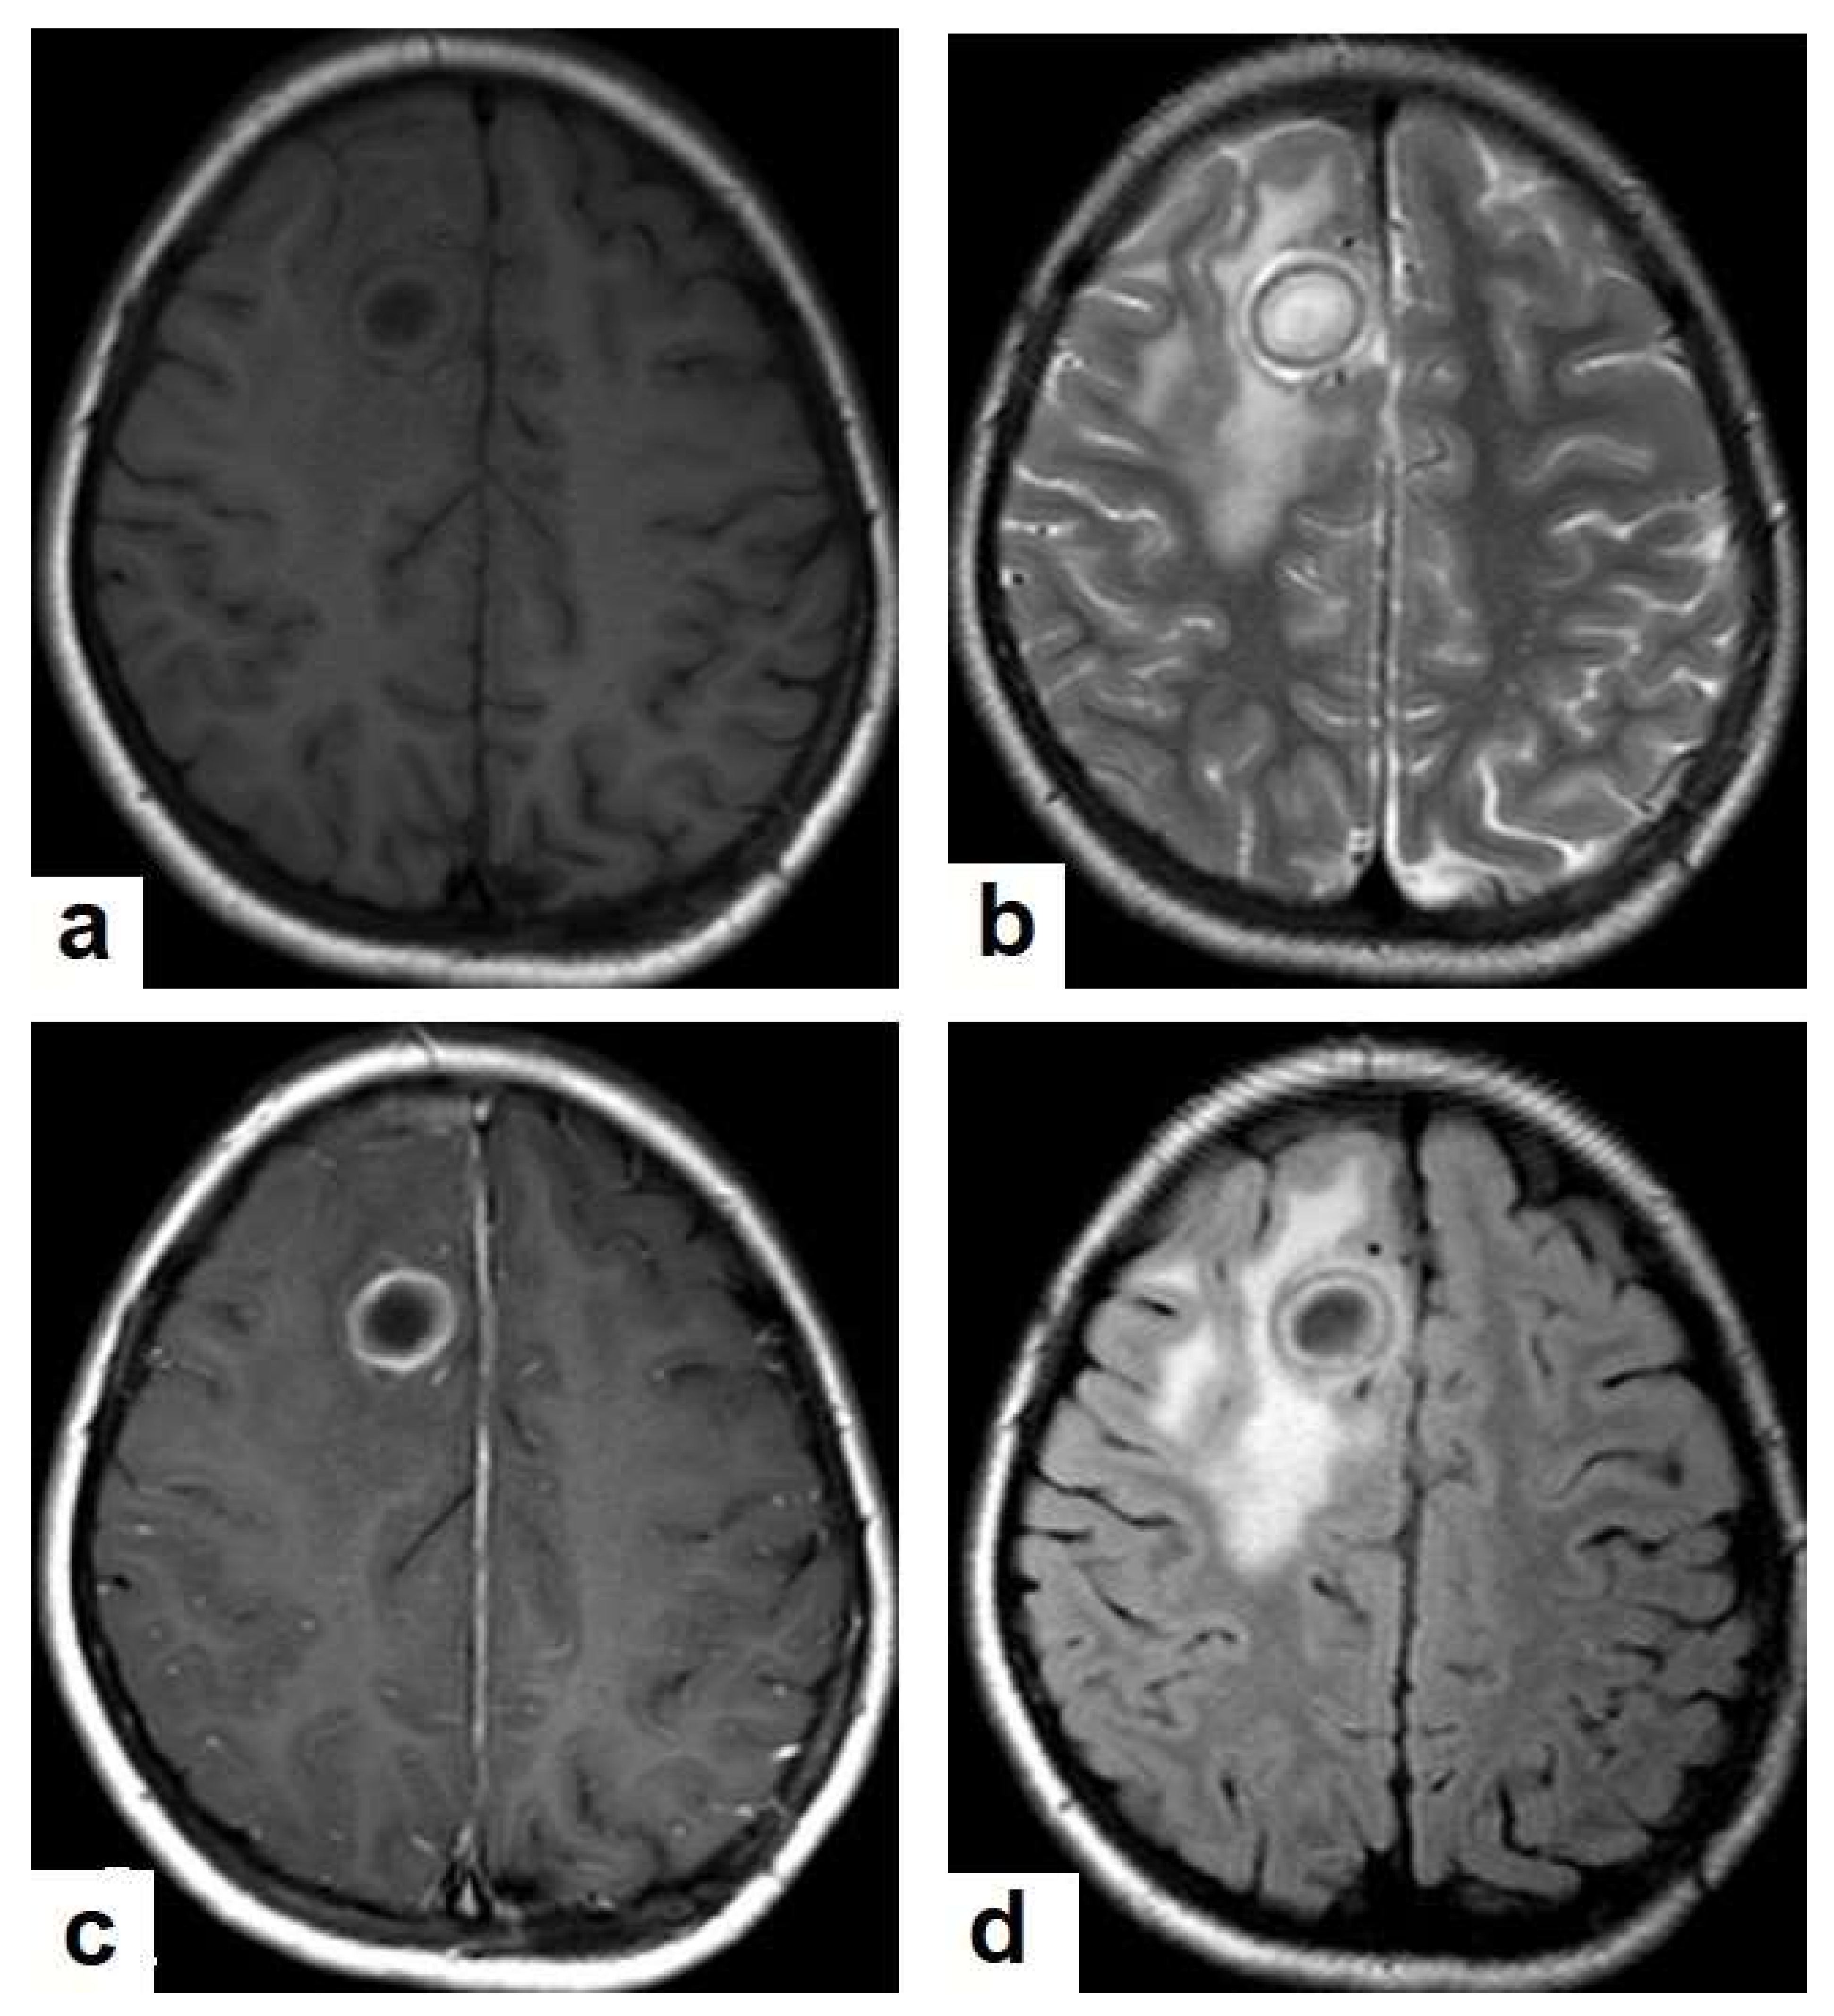

Figure 17. A tuberculous abscess in the cerebellum of a 13-year-old female (same patient as Figure 16). Selected images of brain MRI (a) T1-weighted image (WI), (b) FLAIR-WIs, (c) T1-WI with contrast, and (d) diffusion-weighted (DW) image. The images show a well-defined lesion in the cerebellum with low signal intensity content and a high signal intensity capsule on T1WI and FLAIR (b), marginal enhancement on T1WI with contrast administration (c), and restricted diffusion on DWI (d).

• Tuberculous abscesses (Figure 15, Figure 16 and Figure 17) are an infrequent pattern of brain TB, which are present in immunocompromised and elderly patients. They occur either due to the progression of cerebritis or the liquefaction of tuberculoma. On a brain CT, it occurs as a low density area with ring enhancement after contrast administration and the surrounding low density area of edema. On a brain MRI, it appears as a circular or elliptical area of low intensity with ring enhancement after contrast administration and surrounding low intensity area of edema on T1WIs and high intensity area with a high intensity surrounding edema. Tuberculous abscess is a difficult differential diagnosis of a pyogenic abscess, pilocystic astrocytoma, and other cystic lesions. MR spectroscopy may help in differentiating tuberculous from a pyogenic abscess [27,33].